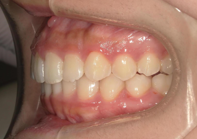

AFTER